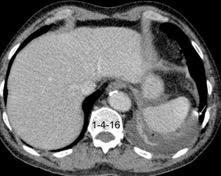

27. DERRAME PLEURAL IZQUIERDO. URINOMA

Enfermedad subdiafragmática Urinoma

Raro. Trasudado.

Orina en espacio pleural

Causas en 78 casos

Trauma……..66

Postcirugía 16

Obstrucción…21 aguda con cálculo e hidronefrosis..12

Freitas A et al. Pleural Effusion Secondary to Obstructive Uropathy: A Case of Urinothorax. Eur J Case Rep Intern Med. 2020/ Toubes ME et al. Urinothorax: a systematic review. J Thorac Dis 2017;

Hidronefrosis con cálculo ureteral